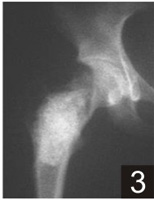

Indications for use:

Product Presentation

|

B-OstIN Granules |

B-OstIN Rod |

B-OstIN Block |